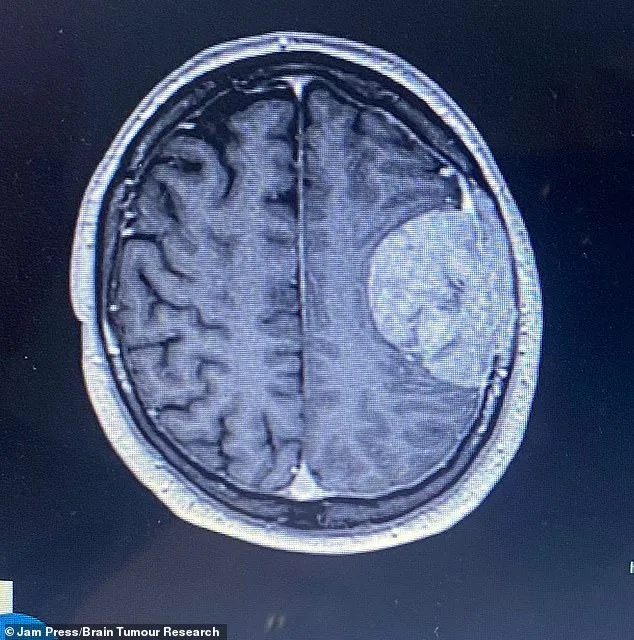

Doctors confirmed the presence of a tumour, but the discovery raised more questions than answers. Because there was no evidence of cancer elsewhere in Stuart's body, surgeons believed the mass was likely a slow-growing tumour he may have lived with for years. 'They warned us the surgery was high-risk,' Bev said. 'There was a chance of another stroke, even death. It was the worst possible news.'

Three weeks later, on May 9, 2025, Stuart underwent a seven-hour operation to remove the tumour. Surgeons successfully extracted the entire growth, which had not spread into the brain itself but was attached to the membrane and skull. Part of his skull was removed and rebuilt using bone cement. 'When I saw him after surgery, he couldn't speak,' Bev said. 'It was heartbreaking. His daughter Megan was taking exams at the time, and it affected her terribly. I don't know how she managed to get through it.'

Initial scans suggested Stuart's speech difficulties were due to post-surgical swelling. However, a later MRI revealed a stroke that had damaged the area of the brain responsible for speech and language. 'He also had a seizure and now takes anti-seizure medication twice a day,' Bev added. Nearly 10 months later, Stuart is still struggling to regain full speech, a reality that has reshaped his family's life.